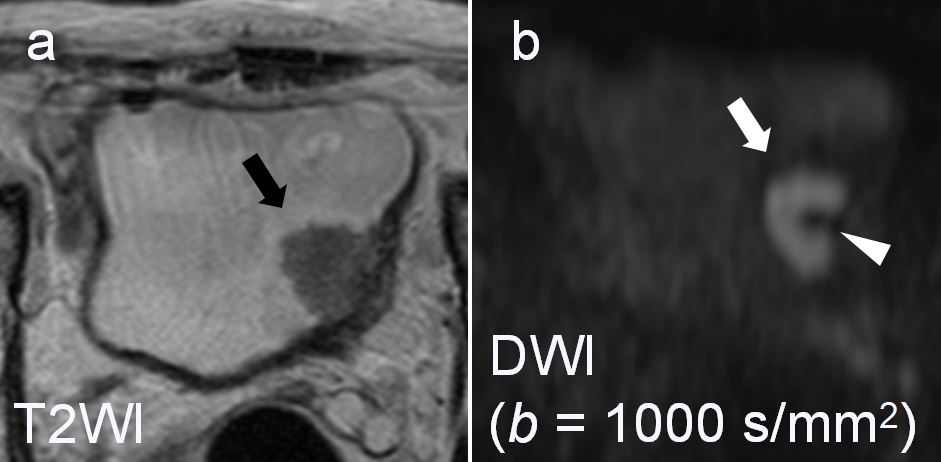

Do you know the Inchworm sign?

This sign is found in case of bladder cancer. It provides information on the degree of microinvasion into the muscularis propria. When absent, the likehood of progression is higher.

Article: Usefulness of the inchworm sign on DWI for predicting pT1 bladder cancer progression